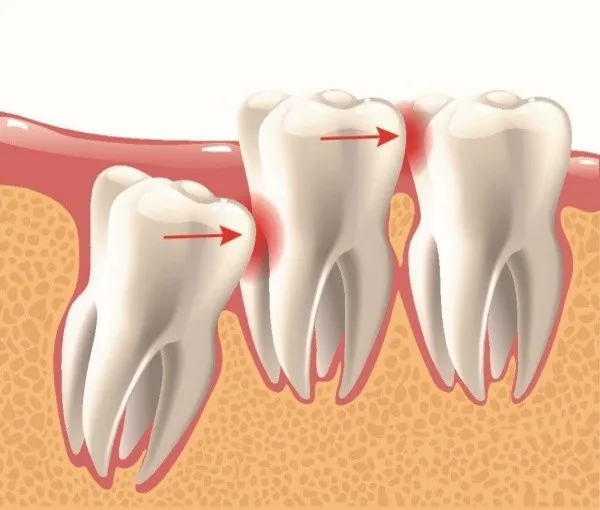

- Theo hướng mọc: Răng có thể mọc lệch theo nhiều hướng khác nhau (ngang, nghiêng gần, nghiêng xa) gây chèn ép mạnh lên chân răng kế cận.

- Chèn ép và Hư hại Răng Kế Cận: Lực đẩy từ răng ngầm, đặc biệt là răng khôn, có thể làm hỏng chân răng số 7 (răng hàm lớn thứ hai), gây tiêu chân răng hoặc sâu mặt bên răng này.

- Lệch Khớp Cắn và Thẩm mỹ: Lực đẩy lâu dài gây xô lệch các răng phía trước, dẫn đến chen chúc, sai lệch khớp cắn, ảnh hưởng lớn đến thẩm mỹ và chức năng ăn nhai.